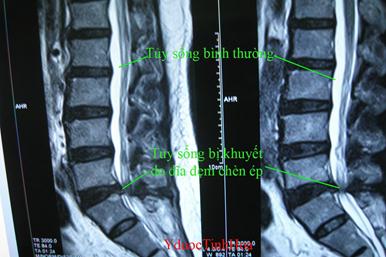

Khi đĩa đệm bị thoát vị sẽ chèn vào rễ thần kinh trong tuỷ sống, ở cổ sẽ đau xuống vai tay, có thể tê xuống các ngón tay bệnh thần kinh. Với thắt lưng sẽ đau xuống thần kinh toạ. Khi bị đau thần kinh toạ sẽ có dấu hiệu đau dọc theo mặt ngoài hoặc mặt sau của mông xuống chân, có thể đau một bên nếu thoát vị lệch về một bên, hoặc đau hai bên nếu thoát vị thể trung tâm.

Trường hợp bác Mai Thị Vận, ĐC số 10 Nguyễn Văn Hoàng, TP Kon Tum khá điển hình. Bác bị đau cổ vai gáy 20 năm nay, gần đây bệnh tăng hơn và lan xuống gây liệt tay trái, điều trị nhiều loại thuốc không những không khỏi mà còn gây đau dạ dày. Trên film chụp MRI bác bị thoát vị đĩa đệm cột sống cổ. Rất may bác được giới thiệu và sử dụng “TINH HOA DƯỠNG CỐT” tay của bác đã vận động trở lại. Nghe bác Mai Thị Vận Tại đây

Cô Vũ Thị Minh ở 76 Cửa Bắc Ba Đình Hà Nội sống ở Anh nhiều năm, cô bị thoái hóa xương khớp gây thoát vị 2 đĩa đệm cột sống thắt lưng, thường xuyên đau nhức, tê buốt từ thắt lưng xuống mông và chân phải. Điều đó ảnh hưởng rất nhiều tới sinh hoạt hàng ngày, vì ở nước Anh thời tiết lạnh và cô phải đi bộ nhiều nên bệnh của cô ngày càng nặng. Mặc dù được tiếp cận nhiều loại thuốc ở châu Âu nhưng cô vẫn phải mang căn bệnh này nhiều năm. Trong khi chờ mổ tại bệnh viện Việt Pháp cô được giới thiệu sử dụng “TINH HOA DƯỠNG CỐT”, bệnh của cô đã hết hẳn đau, vận động bình thường. Sau 2 năm cô trở về Việt Nam đến thăm lại Y Dược Tinh Hoa cô nói rằng cô rất tự hào về nền y học cổ truyền nước nhà. Nghe ý kiến của cô Minh Tại đây Xem sản phẩm TINH HOA DƯỠNG CỐT tại đây Với công nghệ bào chế hiện đại dạng viên nang, việc sử dụng “TINH HOA DƯỠNG CỐT” rất dễ dàng bệnh thần kinh. Mua “TINH HOA DƯỠNG CỐT” cũng thuận lợi vì đã có bán ở khắp các tỉnh thành trong cả nước: Xem địa chỉ mua “Tinh Hoa Dưỡng Cốt” Tại đây